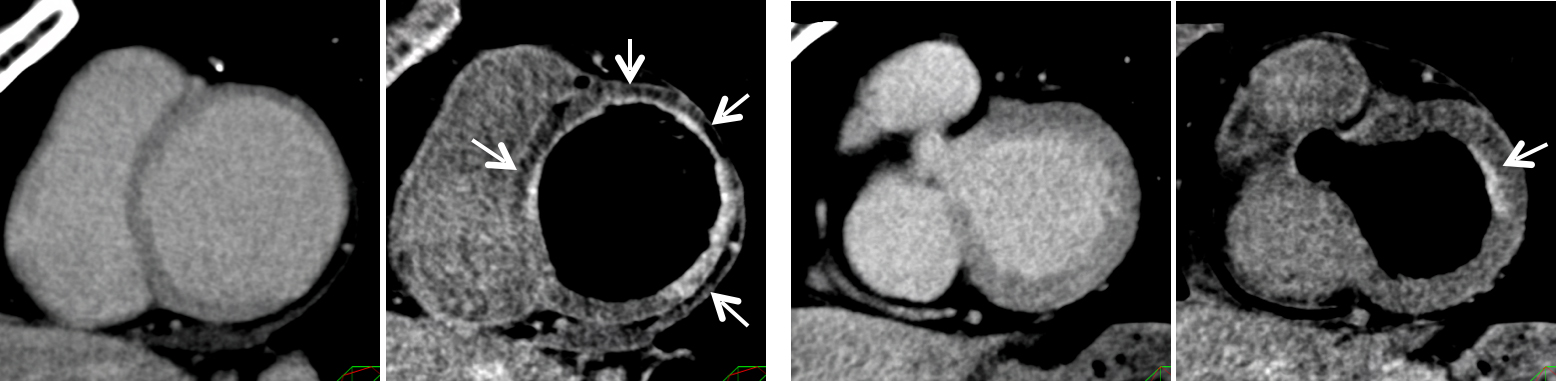

キヤノンメディカルシステムズが開発したPrecise IQ Engine(PIQE)によるディープラーニングの画像によって、冠動脈CT検査で評価が難しい石灰化やステントに接する部分の描出が向上されるため、さらに正確な画像診断が可能となりました。

石灰化症例:左の従来画像と比較して、右の高精細ディープラーニング画像では血管周囲の白い石灰化部分がシャープに描出されています。

ステント症例:左の従来画像と比較して,右の高精細ディープラーニング画像では小さなステントの内部も明瞭に描出されています。

左の従来画像と比較して、右の高精細ディープラーニング画像では矢印の細い血管も明瞭に描出されています。